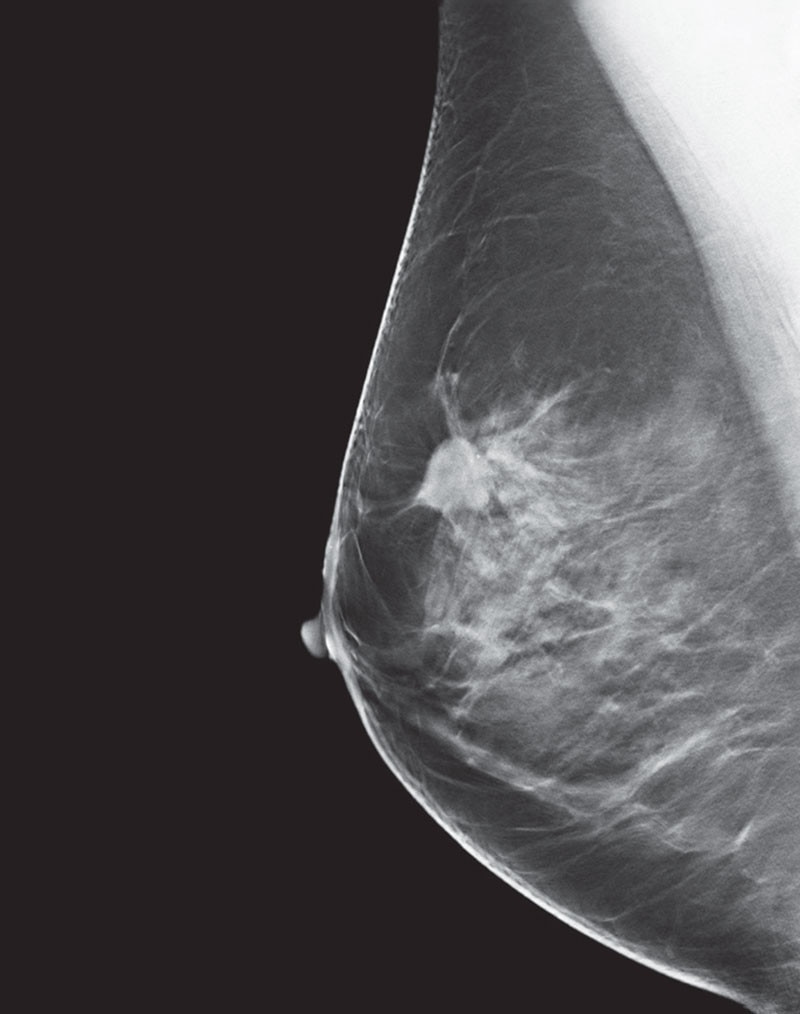

What are the fundamental principles of digital tomosynthesis?

The Fundamental Principles of Digital Radiographic Tomosynthesis interest, barrier-object distance, and radiation dose. The total dose ent reconstruction methods that have been developed. Originally, jection used with CT. Ho wever, this lead to signicant blurring and to the revolutions that occur in CT. Therefore the same principles

What are the features of the GE senoclaire tomosynthesis system?

• Objective: To assess the degree and source of artifacts and to assure that the Flat Field image is Uniform. • 2D Acquisition in Mo/Mo, Mo/Rh, and Rh/Rh modes. • Review Raw Images from Browser • There is a separate Gain Calibration for the MTD to create uniform images.

How big is a GE senoclaire tomosynthesis paddle?

• 3 Available Paddles • 24 x 31, Elevated 24 x 31, Sliding 19 x 23 • 9 images acquired over a 250sweep. • Step and Shoot Acquisition • 100 micron pixel size ‐no binning of pixels • 5:1 Anti‐Scatter grid • MTD attachment weighs over 12 kg and is not counterbalanced ‐use caution if manually moving.